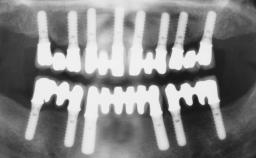

Conventional Loading of Eight Implants in the Maxilla and Final Restoration with a Full-Arch Gold-Ceramic FDP

A 35-year-old Caucasian female presenting with advanced periodontal disease involving both the maxillary and the mandibular dentition was referred for evaluation. The patient, a non-smoker in good general health, requested treatment for recurrent periodontal abscesses, tooth mobility, and discomfort during chewing, as well as restoration of her missing teeth with a fixed prosthesis to improve mastication and esthetics. All residual maxillary teeth exhibited plaque deposits, deep pockets, bleeding on probing, and class III mobility and were evaluated as hopeless. All residual mandibular teeth except tooth 37 could be maintained after periodontal therapy.

# of Implants 8

Type of Implants One-Piece